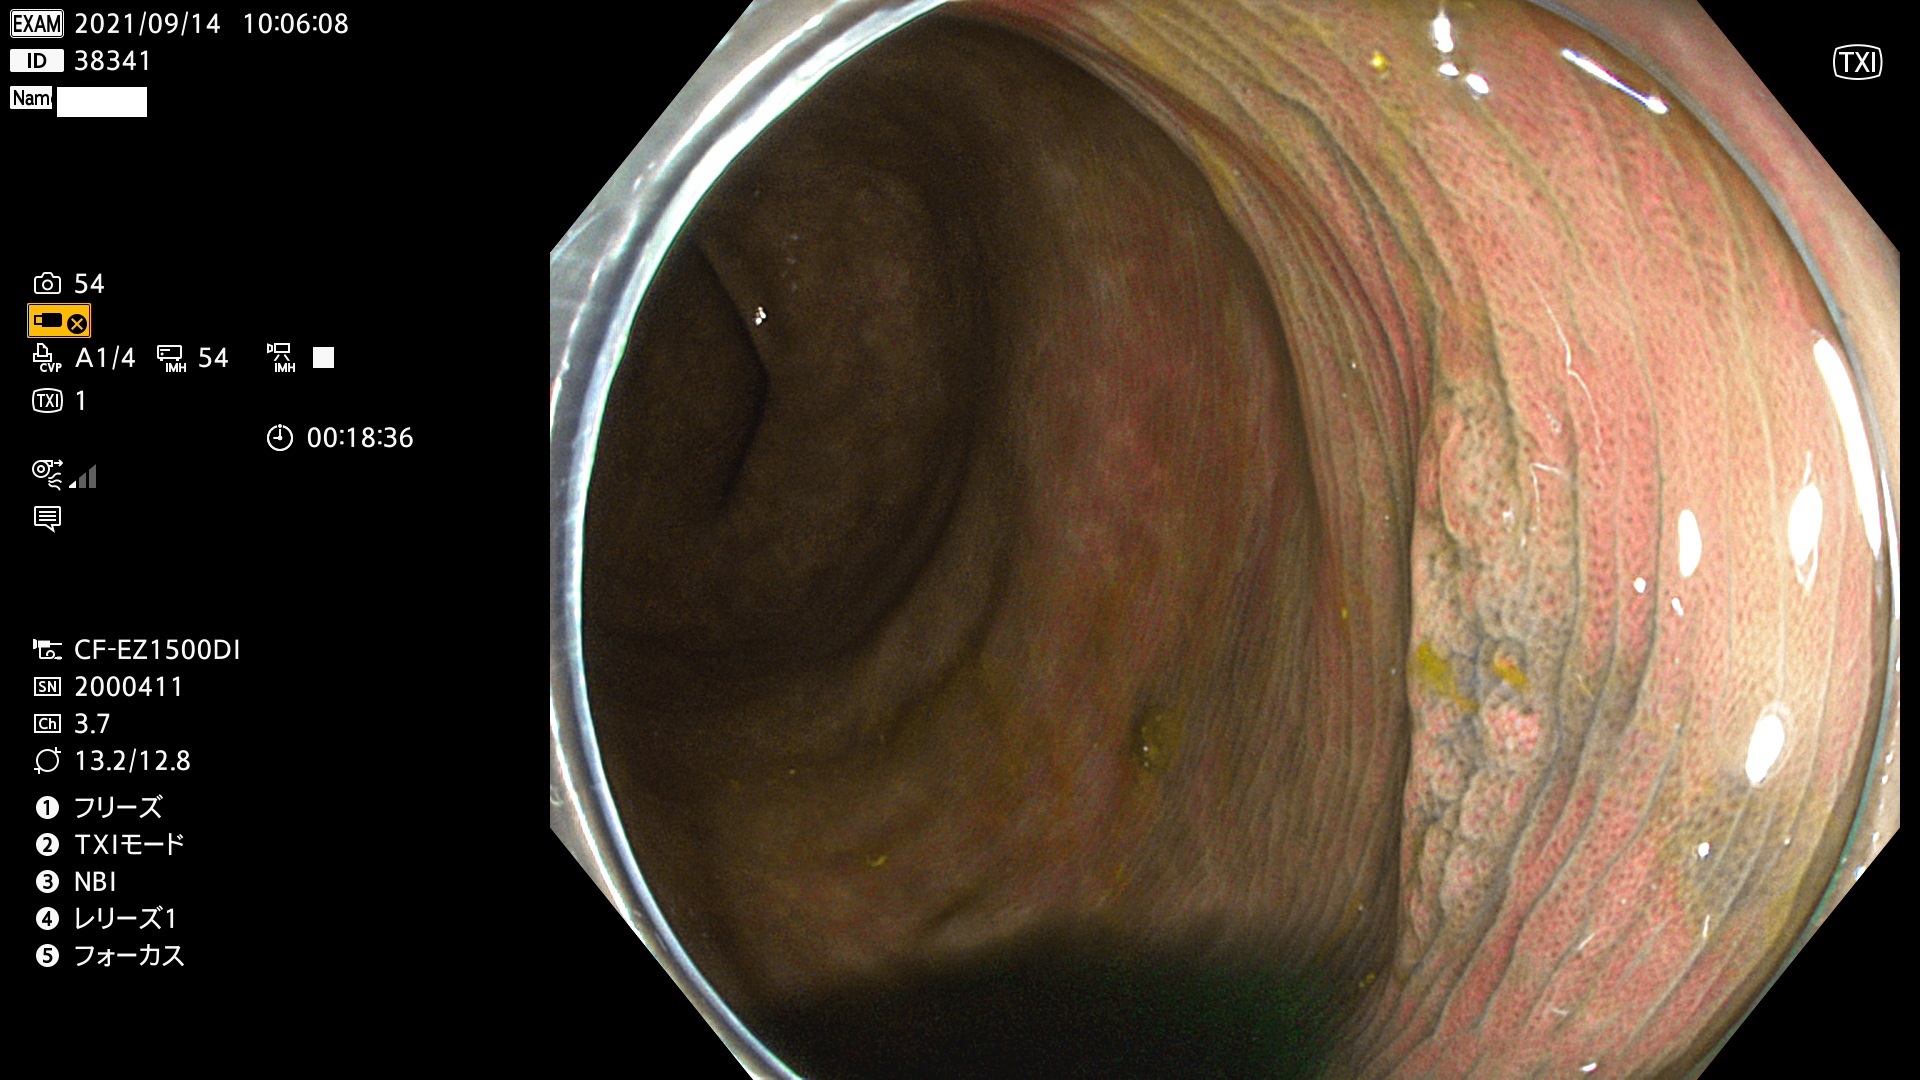

38300 38301 38302 38303 38304 38306 38307 38308 38309 38310 38311 38312 38313 38314 38315 38316 38317 38319 38321 38322 38323 38324 38325 38327 38331 38332 38333 38334 38337 38338 38339 38340 38341 38343 38346 38348 38349 38350 38351 38352 38353 38354 38355 38358 38359 38360 38361 38362 38363 38365 38366(SSAP) 38368 38369 38370 38371(SSAP) 38372 38374 38375 38376 38377 38378 38380 38381 38382 38383 38384 38385 38386 38388 38389 38391(SSAP) 38395 38397 38399

発見困難で危険性の高い平坦型病変(上記100名より抽出)